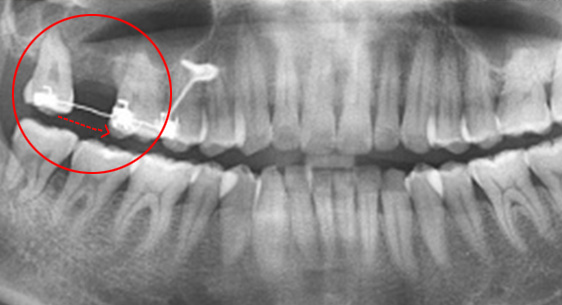

대부분의 치과에선 빼야하는 치아가 있거나 이미 빠졌거나, 신경 치료 후 예후 불량으로 인해 치아를 살릴 수 없는 경우 임플란트를 먼저 고려합니다.

고운미소치과는 인접치아를 움직여 그 공간을 닫아 임플란트 수술이나 보철 치료 없이 자연치를 최대한 활용하는 치료 계획을 세웁니다.

치조골 손상이 심해 발치를 하고 임플란트를 해야하는 상황

인접치아로 발치된 공간을 메꿈

자연치보존 교정치료